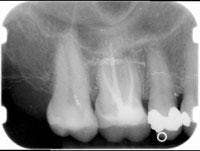

A 48-year-old woman presented with pain in her upper right quadrant. After taking her history and a radiograph, pulp testing confirmed irreversible pulpitis on Tooth No. 4 (Figure 1).